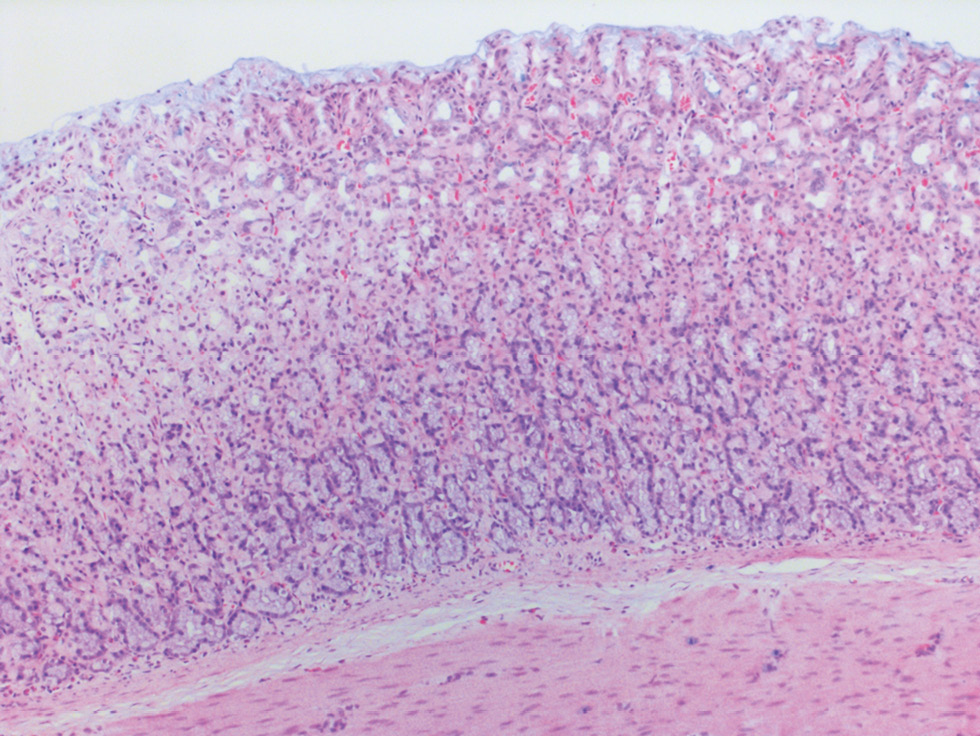

In the morphological study of rats in the control group, we observed high villi in the GMM, shallow dimple-cervical regions, a uniform distribution of glands, and single lymphocytes in the mucous membrane. We also noted that the muscular layer is represented by bundles of smooth muscle fibers, while the serous membrane is covered with a single layer of mesothelium. The thickness of the mucous membrane of the stomach body was 0.50 ± 0.01 mm, while that of the antrum was 0.30 ± 0.03 mm. Histochemical detection of glycosaminoglycans using Alcian blue stain at pH 2.5 in the stomach body revealed focal, poorly expressed production by the epithelium of the superficial parts of the GMM. On the other hand, focal production of glycosaminoglycans in the antrum section was observed in the bottom sections of the glands (Figs. 1, 2).

Fig. 1. Control group rat. Gastric body mucosa1 / Рис. 1. Крыса группы контроля. Слизистая оболочка тела желудка2

1 In the pictures 1–4 histology slides stained with hematoxylin and eosin with alcian blue additional staining, ×200 magnification.